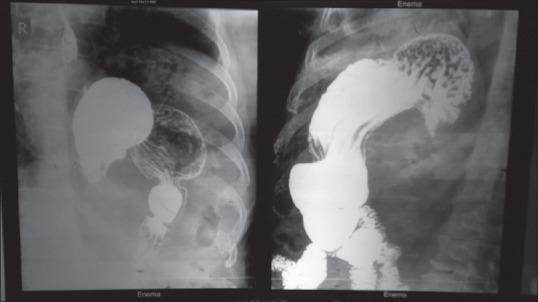

胃扭转在临床表现、诊断、影像学支持、病理行为和评价等方面具有不同的意义,是一种罕见的医学实体,对诊断和治疗的怀疑指数要求很高。当急性出现时,很容易被发现。然而,在亚急性表现的患者中,由于发作性扭转和解扭转,症状模糊。如果在症状期进行影像学检查,可以建立明确的术前诊断。本报告的主要目的是强调有必要对这种疾病保持高度的怀疑指数,并在症状期间对患者进行成像。

Gastric volvulus is a rare medical entity that requires high index of suspicion for diagnosis and treatment as it has different implications in terms of clinical presentation, diagnosis, imaging support, pathological behavior, and evaluation. When it presents acutely, it may be easily detected. However, in patients with subacute presentation, symptoms are vague due to episodic twisting and untwisting. Definite preoperative diagnosis can be established if imaging is performed during symptomatic interval. The main aim of this report was to stress on the need for keeping high index of suspicion for this medical condition and for imaging the patient during symptomatic interval.